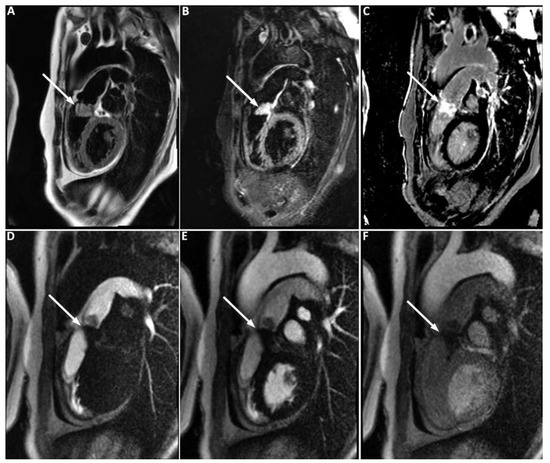

Pulmonary artery sarcomas are uncommon intracardiac tumours with poor prognosis. We report the case of a 69-year-old woman in good health presenting with rapidly progressive dyspnoea and an unfamiliar systolic murmur. Echocardiography revealed pulmonary valve stenosis due to an obstructing mobile mass. Imaging [...] Read more.

Pulmonary artery sarcomas are uncommon intracardiac tumours with poor prognosis. We report the case of a 69-year-old woman in good health presenting with rapidly progressive dyspnoea and an unfamiliar systolic murmur. Echocardiography revealed pulmonary valve stenosis due to an obstructing mobile mass. Imaging studies confirmed the presence of a contrast-enhancing lesion adherent to the valve, extending into the pulmonary trunk and right ventricular outflow tract, and suggestive of malignancy. Endovascular biopsy was attempted with no success. Surgical resection with autologous graft valve replacement and pulmonary artery reconstruction was performed. Postoperative histological examination confirmed the diagnosis of an undifferentiated pleomorphic sarcoma. Pulmonary artery sarcoma should be considered as a rare differential diagnosis in patients presenting with dyspnoea and a crescendo–decrescendo systolic murmur increasing with inspiration. Echocardiography is a useful first diagnostic approach but multi-imaging assessment is almost always necessary for definite diagnosis. Our case provides insights into the challenges met by cardiologists, radiologists and cardiac surgeons in the management of such cases. Full article

Show Figures

Figure 1